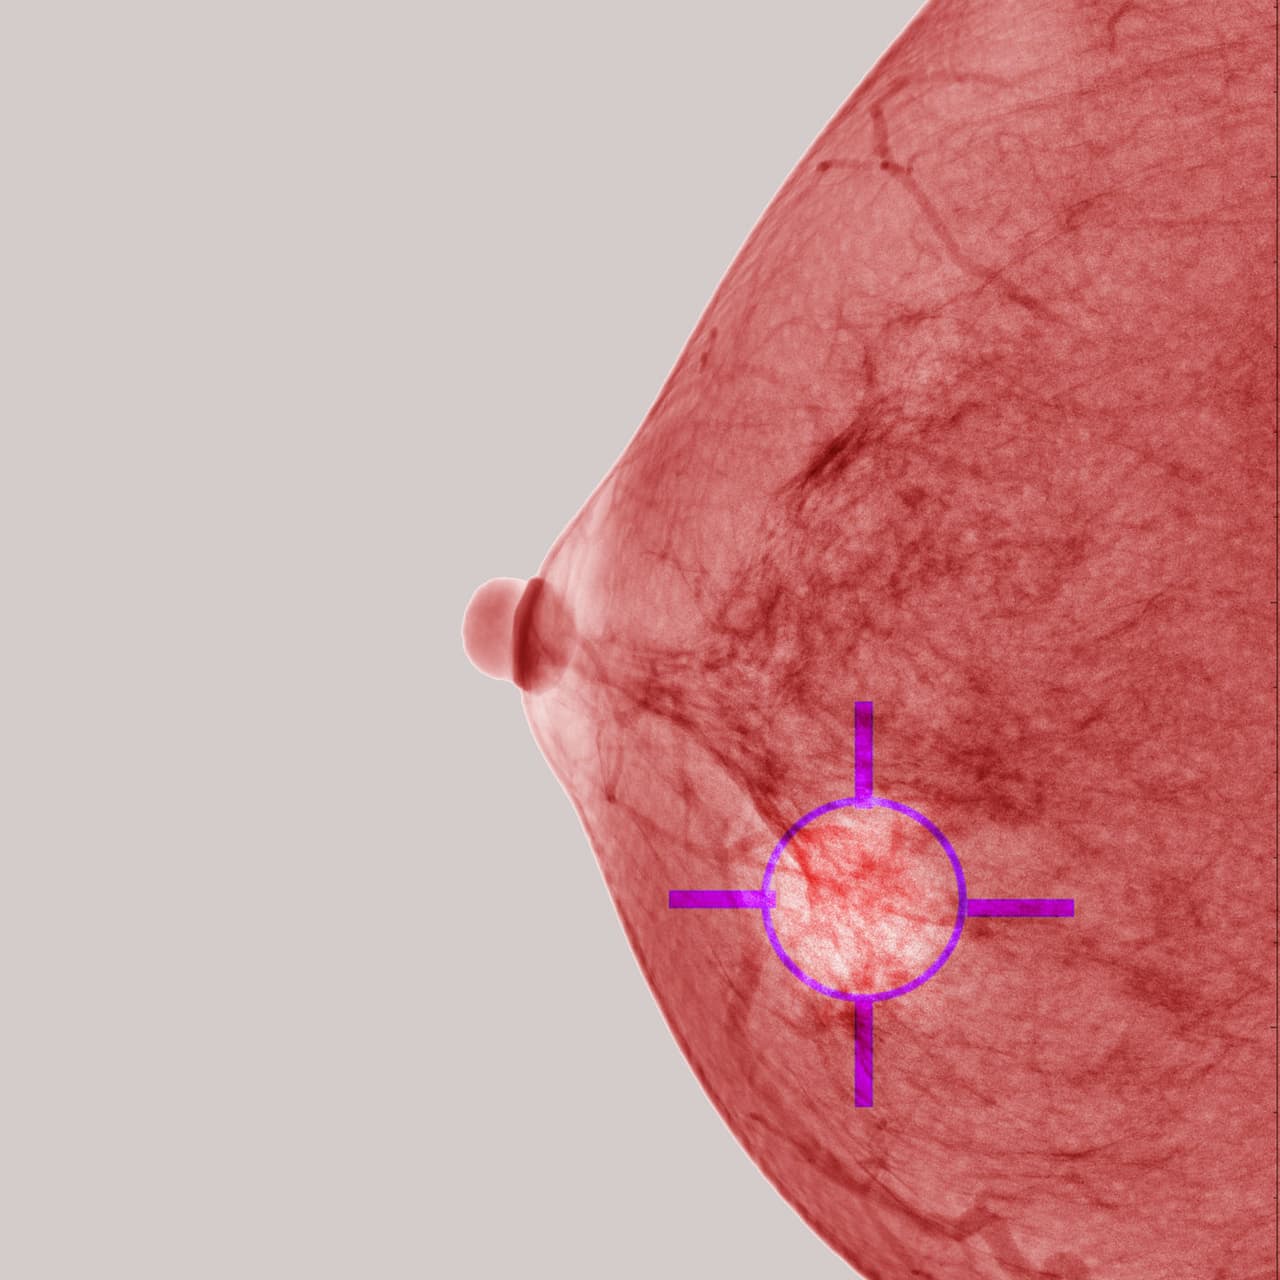

El cáncer de mama es el tipo de cáncer más común entre las mujeres de todo el mundo, de cualquier edad y nacionalidad. Es la principal causa de muerte por cáncer en mujeres. El riesgo de padecerlo responde a causas genéticas, también la complexión de la propia mujer y la forma de sus senos, su segregación de hormonas o cuándo haya empezado a menstruar, entre muchos otros factores, de acuerdo con la American Cancer Society.

El autoexamen de mama a través del tacto es la manera más divulgada de detectar el cáncer de mama, pero no siempre el tumor puede ser percibido solamente palpando los senos. Hay síntomas que no tienen nada que ver con tener un bulto en la región.

Debes prestarle suficiente atención a tu cuerpo y realizarte exámenes preventivos frecuentemente, como la mamografía. Estas son medidas esenciales para un diagnóstico rápido y certero de cáncer. Si se descubre en las fases iniciales, el cáncer de mama tiene 98 % de chances de cura.